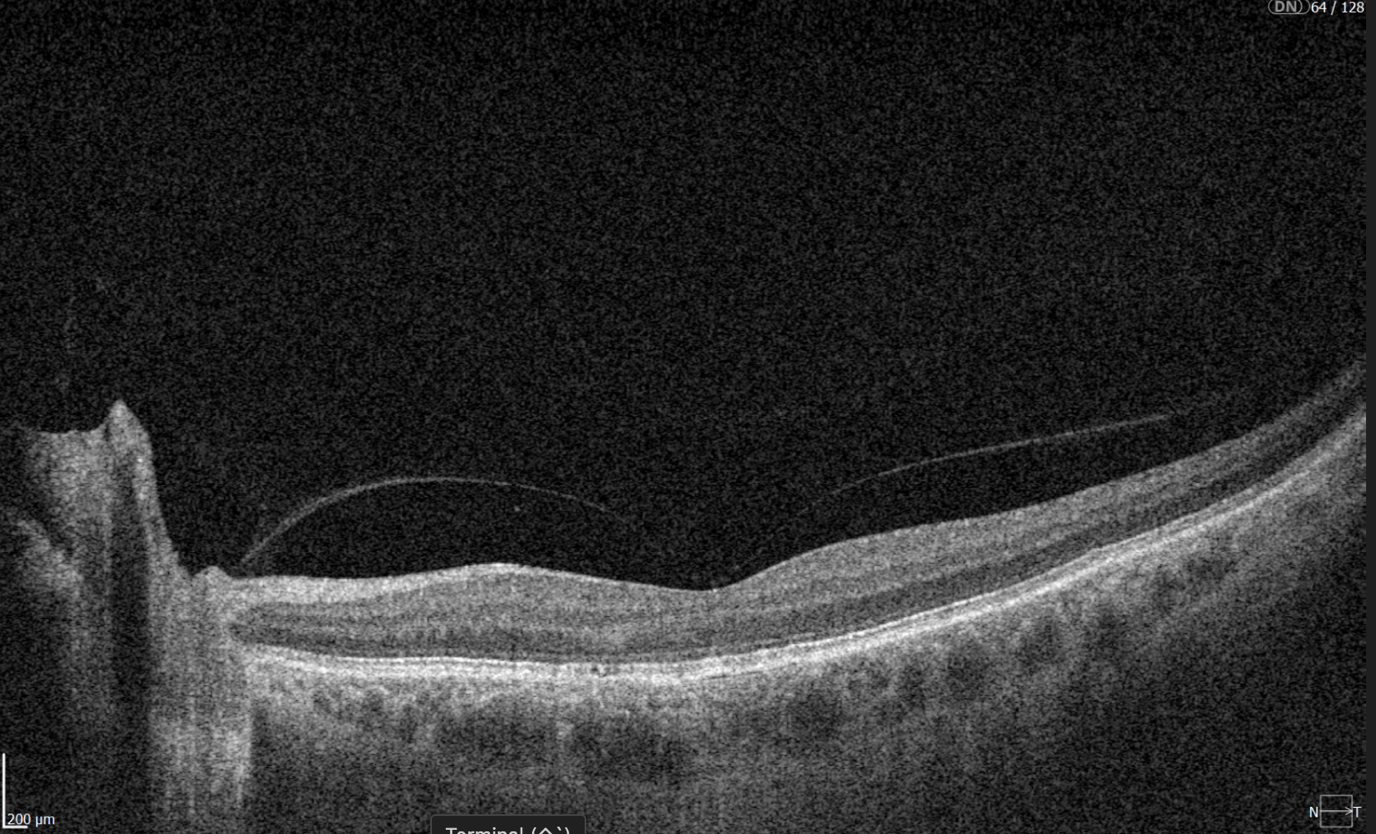

Screening DR with OCT

Diabetic retinopathy (hyperreflective foci, microaneurysms, destruction of the ellipsoid zone and RPE), diabetic macular edema (neuroepithelial swelling, intraretinal cystic cavities), epiretinal membrane.

Monitoring of diabetic retinopathy progression

Ongoing diabetic retinopathy monitoring is essential to detect early signs of progression and guide treatment decisions. A key focus in monitoring is diabetic macular edema (DME), which represents fluid accumulation in the macula due to leakage from damaged retinal vessels. DME is a common complication of DR and the leading cause of vision loss in diabetic patients. OCT plays a central role in detecting DME and identifying structural changes that indicate disease progression.